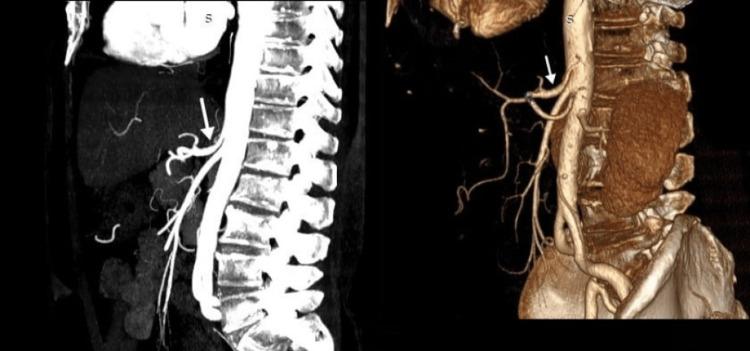

Celiac artery compression syndrome (CACS) is an uncommon and poorly understood condition. Compression of the celiac artery by the median arcuate ligament causes intractable postprandial abdominal pain, weight loss, vomiting, and nausea. We present a case of a 68-year-old male who suffered recurrent severe episodes of postprandial abdominal pain associated with occasional nausea, vomiting, and elevated blood pressure. The diagnostic workup was significant for celiac artery compression on computed tomography angiography. Diagnosis of CACS was made after the exclusion of the other possible pathologies, and the patient was referred to the surgical team for further management for median arcuate ligament release on an elective basis.

腹腔干压迫综合征(CACS)是一种罕见且了解甚少的病症。正中弓状韧带对腹腔干的压迫会导致顽固性餐后腹痛、体重减轻、呕吐和恶心。我们报告一例68岁男性患者,他反复出现严重的餐后腹痛发作,伴有偶尔的恶心、呕吐和血压升高。计算机断层血管造影显示腹腔干受压,这在诊断检查中具有重要意义。排除其他可能的病理情况后,确诊为CACS,该患者被转介至外科团队,择期进行正中弓状韧带松解的进一步治疗。